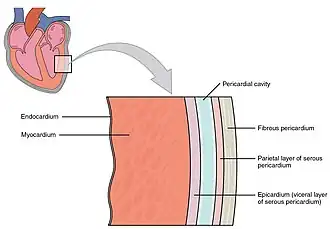

O coração humano divide-se em quatro cavidades. Na parte superior situam-se as aurículas direita e esquerda e, na parte inferior, os ventrículos direito e esquerdo.[4][5] É comum designar o conjunto da aurícula e do ventrículo direitos por "coração direito" e o conjunto equivalente do lado esquerdo por "coração esquerdo".[6] Num coração saudável, as válvulas cardíacas fazem com que o sangue dentro do coração flua em sentido único, impedindo o seu refluxo.[3] O coração é envolvido pelo pericárdio, uma membrana protetora em forma de saco que contém uma pequena quantidade de líquido. A parede do coração é constituída por três camadas: o epicárdio, o miocárdio e o endocárdio.[7] O coração dos restantes mamíferos e das aves apresenta igualmente quatro cavidades.[4] O coração dos peixes apresenta apenas duas cavidades, uma aurícula e um ventrículo, enquanto o dos répteis apresenta três cavidades.[5]

Parede cardíaca

A parede do coração é constituída por três camadas: o endocárdio, o miocárdio e o epicárdio. Estas camadas estão envolvidas por um saco com duas membranas denominado pericárdio. O endocárdio é a camada mais interior do coração. É constituída por um revestimento de tecido epitelial escamoso simples e reveste as cavidades e as válvulas cardíacas. Forma uma camada contínua com o endotélio das veias e das artérias e encontra-se unida ao miocárdio por uma camada fina de tecido conjuntivo.[7] O endocárdio segrega endotelina, que pode ter uma função na regulação da contração do miocárdio.[7]

A camada intermédia da parede do coração é o miocárdio, que é o músculo cardíaco. Trata-se de uma camada de tecido muscular estriado envolvida por uma estrutura de colagénio. O padrão do músculo cardíaco é intrincado e complexo, de modo a permitir ao coração bombear sangue com maior eficácia. As células musculares fazem uma espiral à volta das cavidades do coração, em que os músculos exteriores formam um 8 à volta das aurículas e das bases dos grandes vasos, e os músculos interiores formam um 8 à volta dos dois ventrículos em direção ao ápice.[7]

O pericárdio envolve o coração e é constituído por duas membranas: uma membrana serosa interna denominada epicárdio e uma membrana fibrosa externa. Por sua vez, o epicárdio, divide-se em pericárdio visceral e pericárdio parietal. Dentro destas camadas existe a cavidade pericárdica, que contém o liquido pericárdico que lubrifica o coração.[7][18] O pericárdio ajuda a regular o ritmo cardíaco e é através do epicárdio que os vasos sanguíneos e os nervos irrigam o músculo cardíaco.[7]